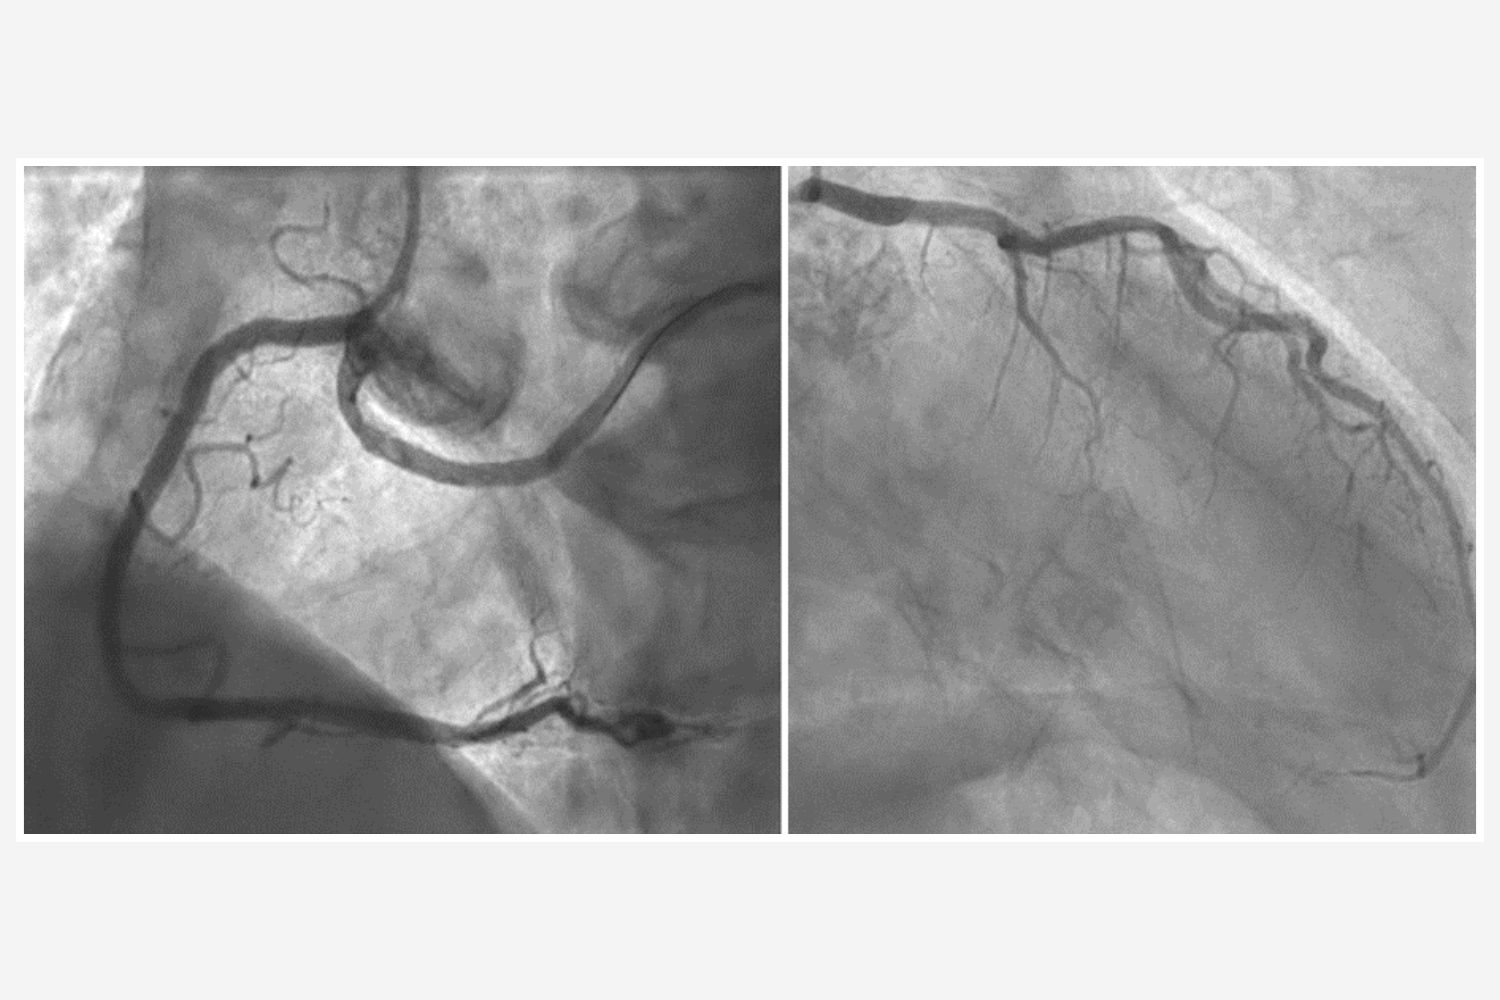

Image of the Week 21 January 2026

Image of the week